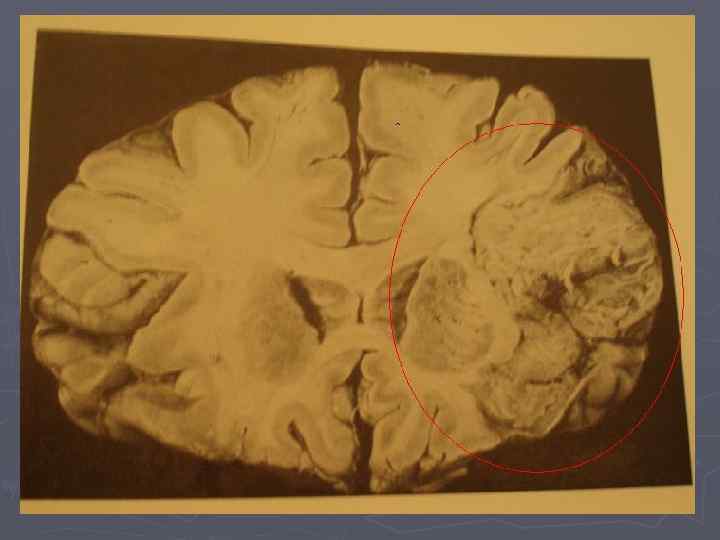

► Геморрагичес кий инсульт (макросрез)